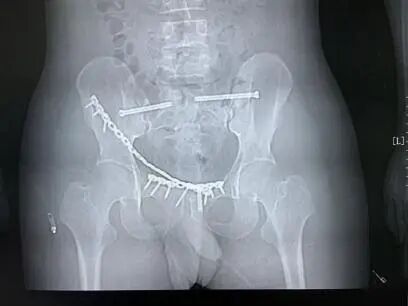

为了减少骨盆骨折相关并发症的发生,提高治疗效率,王金台主任决定为患者采用耻骨骨折、耻骨联合分离有限切开复位内固定术+CT引导下微创骶髂螺钉内固定术治疗。

面对复杂危重的病情,王金台主任团队迎难而上,联合ICU、普外科等多学科会诊,全面评估手术风险与应对策略。最终,在手术室、麻醉手术部及影像科秦伟副主任医师的高效协作下,手术顺利实施,为患者后续康复奠定了坚实基础。目前患者恢复良好,已顺利出院。

术后CR